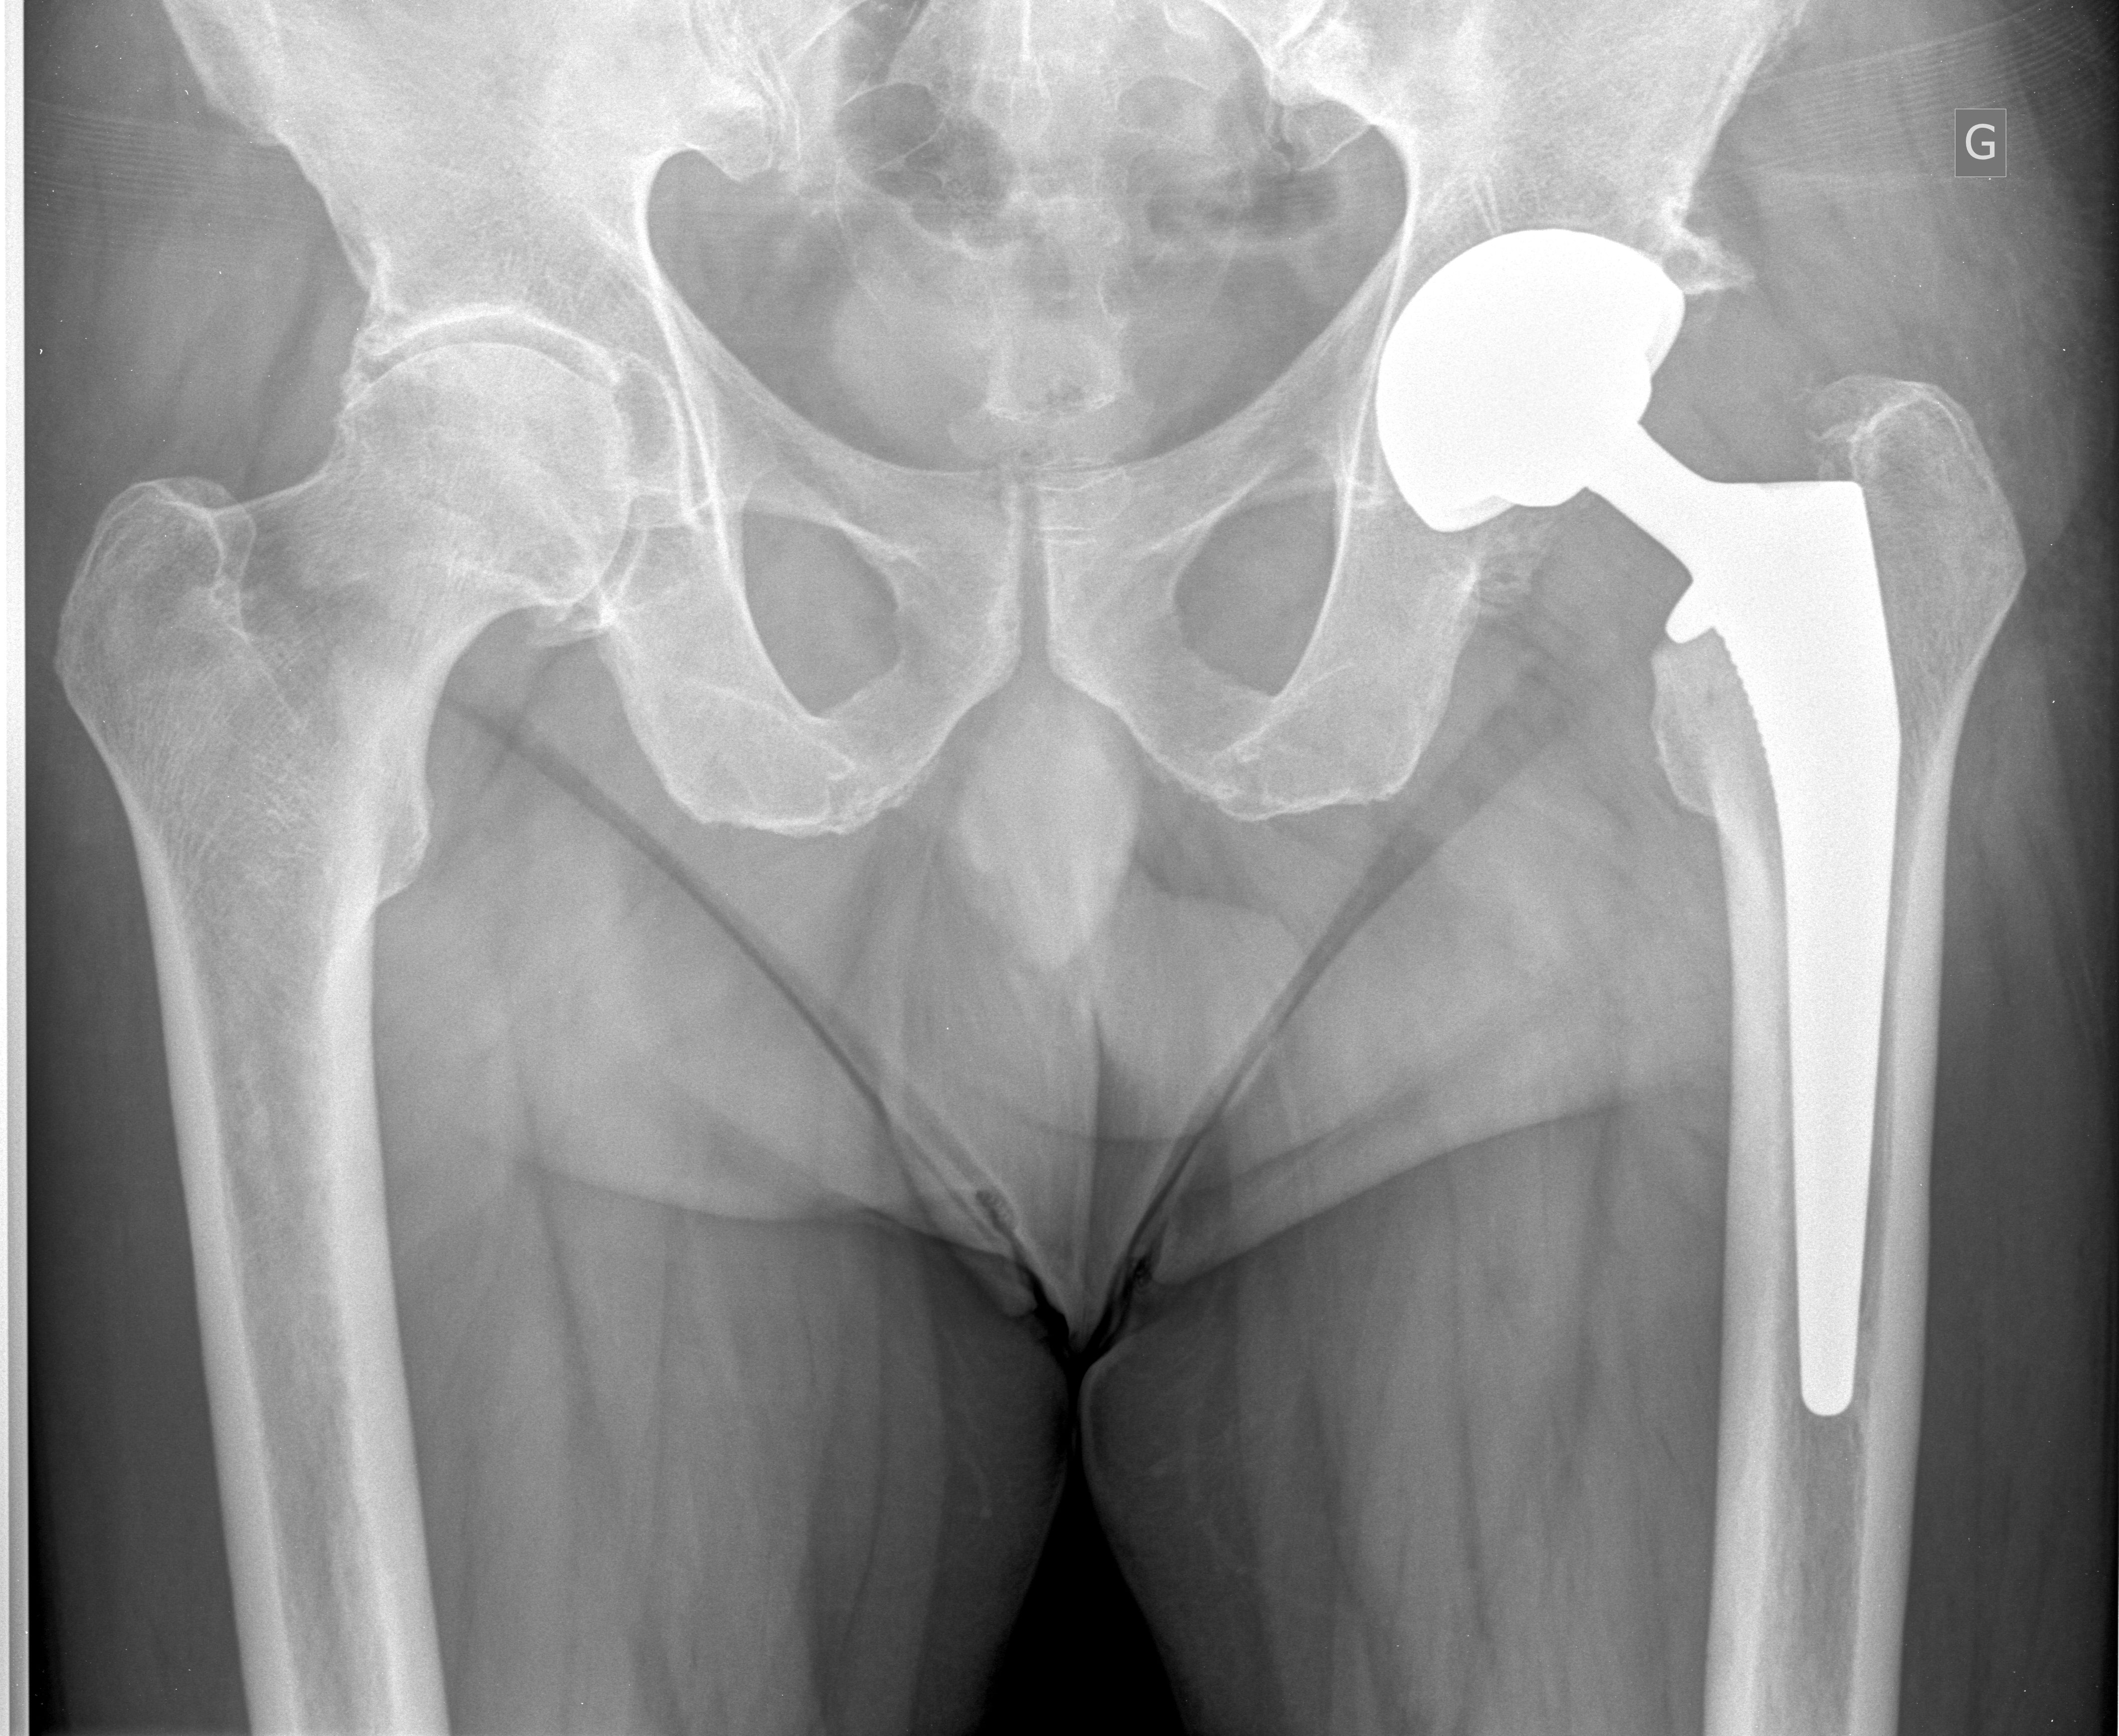

L’intervention de prothèse de hanche – Docteur Gaël Poirée Nice Published on 15 mai 2017 in L’intervention de prothèse de hancheFull resolution (4248 × 3480) L’intervention de prothèse de hanche – Docteur Gaël Poirée Nice